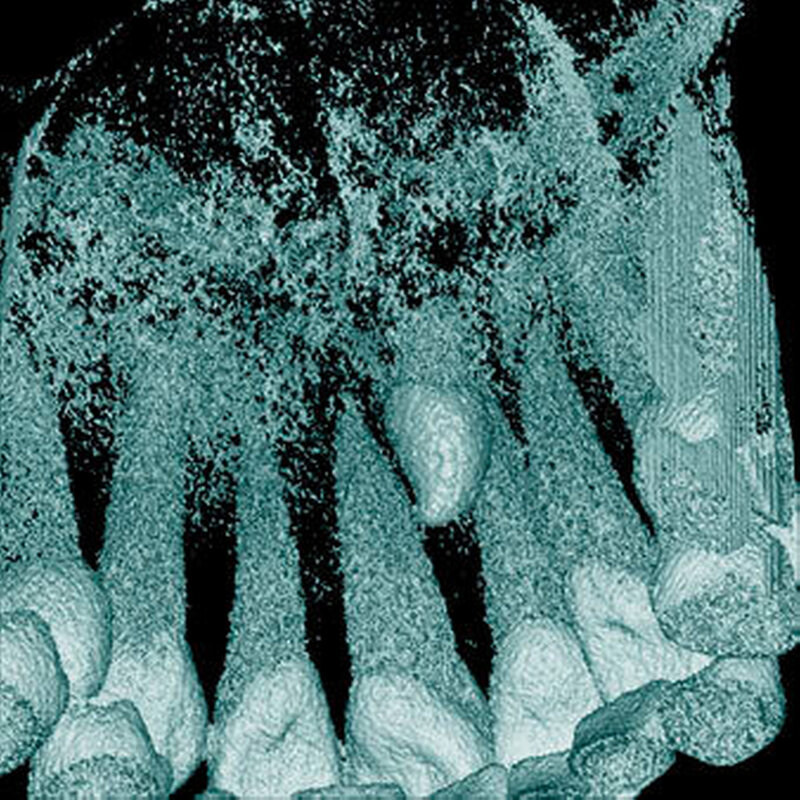

Überzählige Zähne können einzeln oder multipel auftreten [von Arx, 1990; Rajab Hamdan, 2002; Fernández Montenegro et al., 2006; Liu et al., 2007; Gündüz et al., 2008; Ferrés-Padró et al., 2009; Hyun et al., 2009]. Einzelne überzählige Zähne treten in 65,8 bis 80,5 Prozent, doppelte in 14,5 bis 27,7 Prozent und multiple in 0,6 bis 8 Prozent der Fälle auf [Rajab Hamdan, 2002; Fernández Montenegro et al., 2006; Liu et al., 2007; Ferrés-Padró et al., 2009; Hyun et al, 2009; Mossaz et al., 2014]. Einzelne oder doppelte überzählige Zähne finden sich typischerweise in der Oberkieferfront [Rajab Hamdan, 2002; Fernández Montenegroet al., 2006; Mossaz et al., 2014]. Multiple überzählige Zähne werden vor allem im Prämolarenbereich des Unterkiefers gefunden [Abbildung 4; YUSOF 1990, Ferrés-Padróet al., 2009; Wang Fan, 2011]. Multiple überzählige Zähne sind zudem oft mit anderen Erkrankungen oder Syndromen assoziiert, dazu gehören Lippen-Kiefer-Gaumenspalten, die cleidokraniale Dysplasie oder auch das Gardner-Syndrom. Bei Patienten mit einer Lippen-Kiefer-Gaumenspalte wird vermutet, dass sich die überzähligen Zähne aus der Fragmentierung der dentalen Lamina bei der Spaltbildung ergeben [Garvey et al., 1999; Wang Fan, 2011].